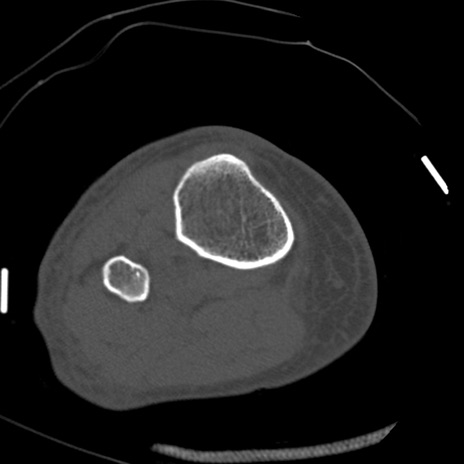

症例28 右膝関節CT(横断像)

右膝関節CT